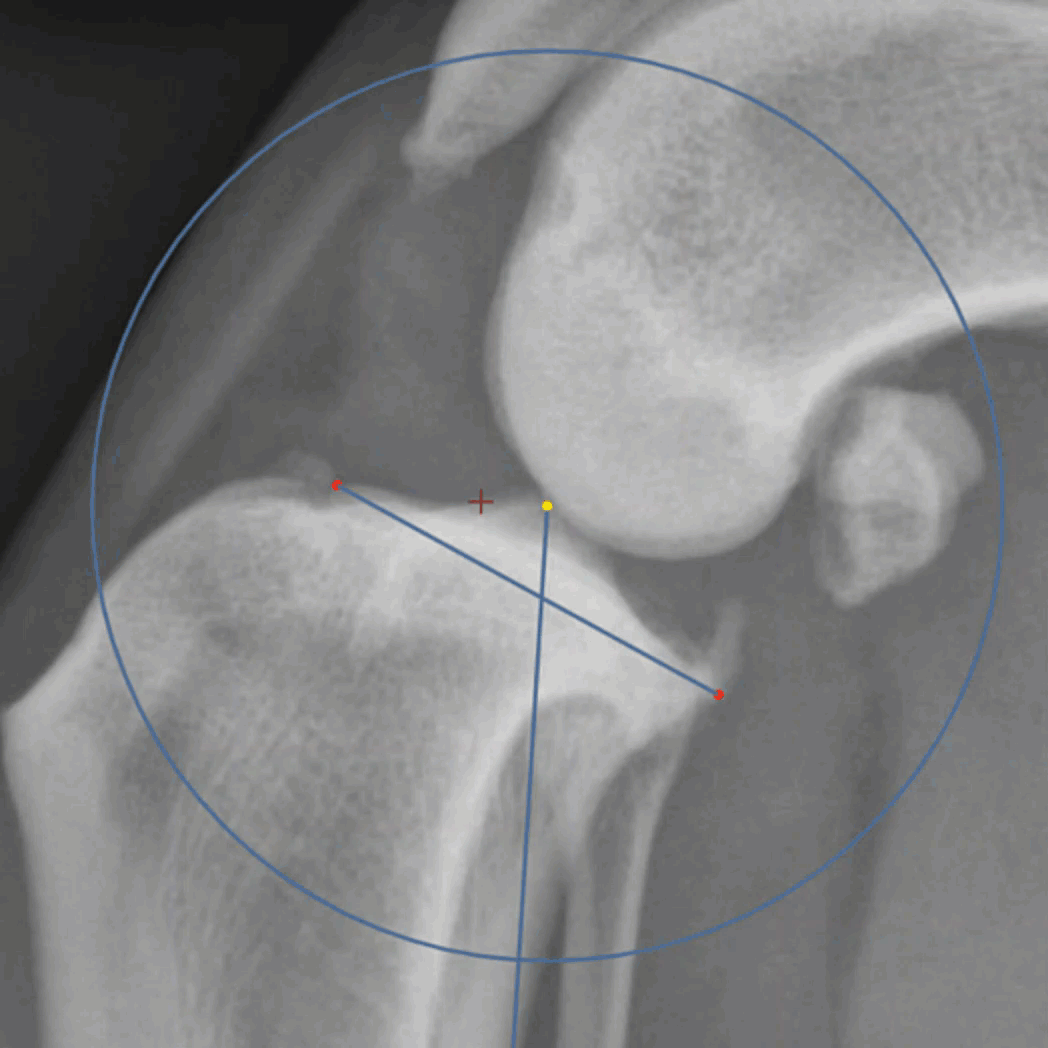

Magnetic

The magnetic cut tool will start with the user performing a single click and drag. Shortly after a line will appear between the initial point and the current location of the mouse. This tool finds the path from the last point to the cursor with the highest contrast. Often this will be along measurement lines. To confirm good locations, where the green line is on the desired path, release the drag to confirm and then click again to start the next segment of the line. This will result in a series of segments of drag and drops to confirm correct locations.

As with all of the cutout tools, the center of rotation can be modified and the 0 degree marker is the grab point from which the cut shape will rotate. click within the shape and drag to move the fragment within the viewport.

Since the Magnetic cut tool snaps to lines, performing a cut along the entire perimeter of the blade is a quick way to cut and rotate a fragment.